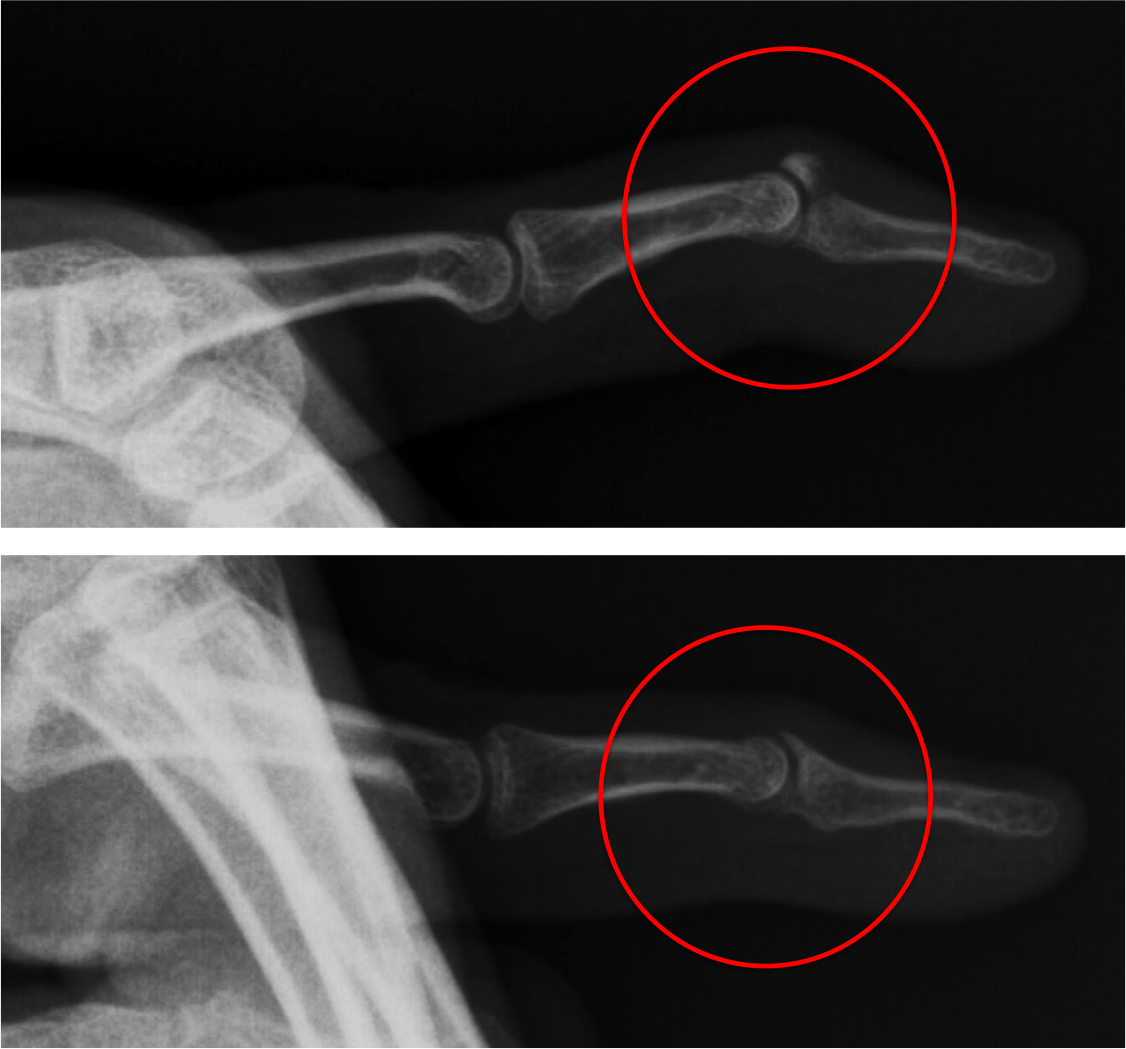

From radiopaedia.org

Mallet finger Image Mallet Finger Nice Le mallet finger (ou doigt en maillet) est une maladie extrêmement fréquente. A mallet finger injury is a tear of tendon that straightens the end joint of the finger. If you have mallet finger, you’re unable to straighten your finger, it droops at the tip, is painful and looks bruised and/or swollen. A mallet finger is a deformity of the. Mallet Finger Nice.